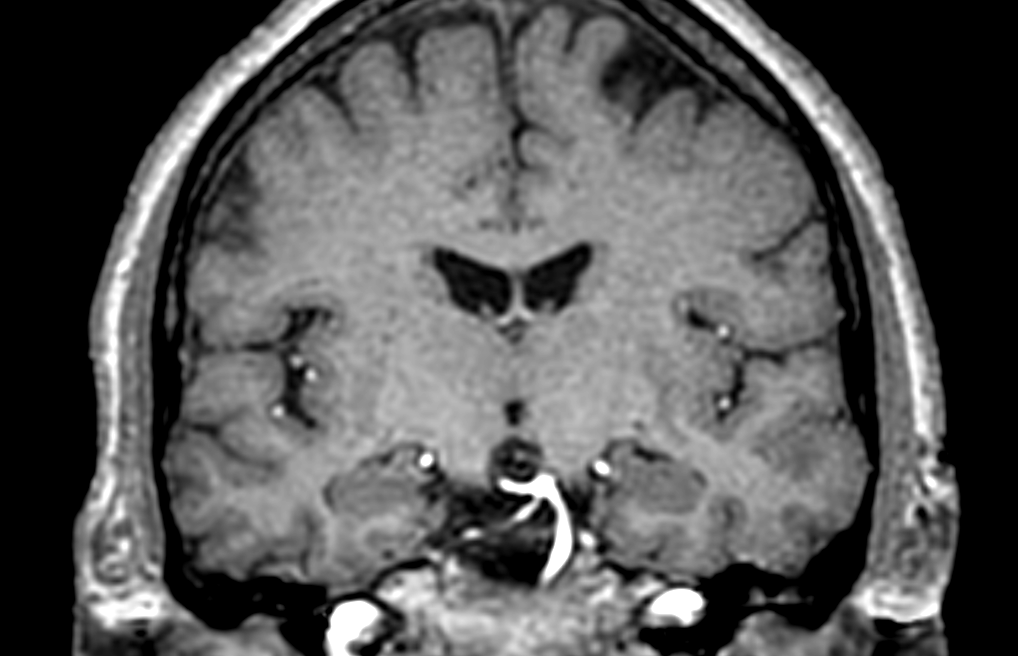

3D T1w TFE (coronal reformat)